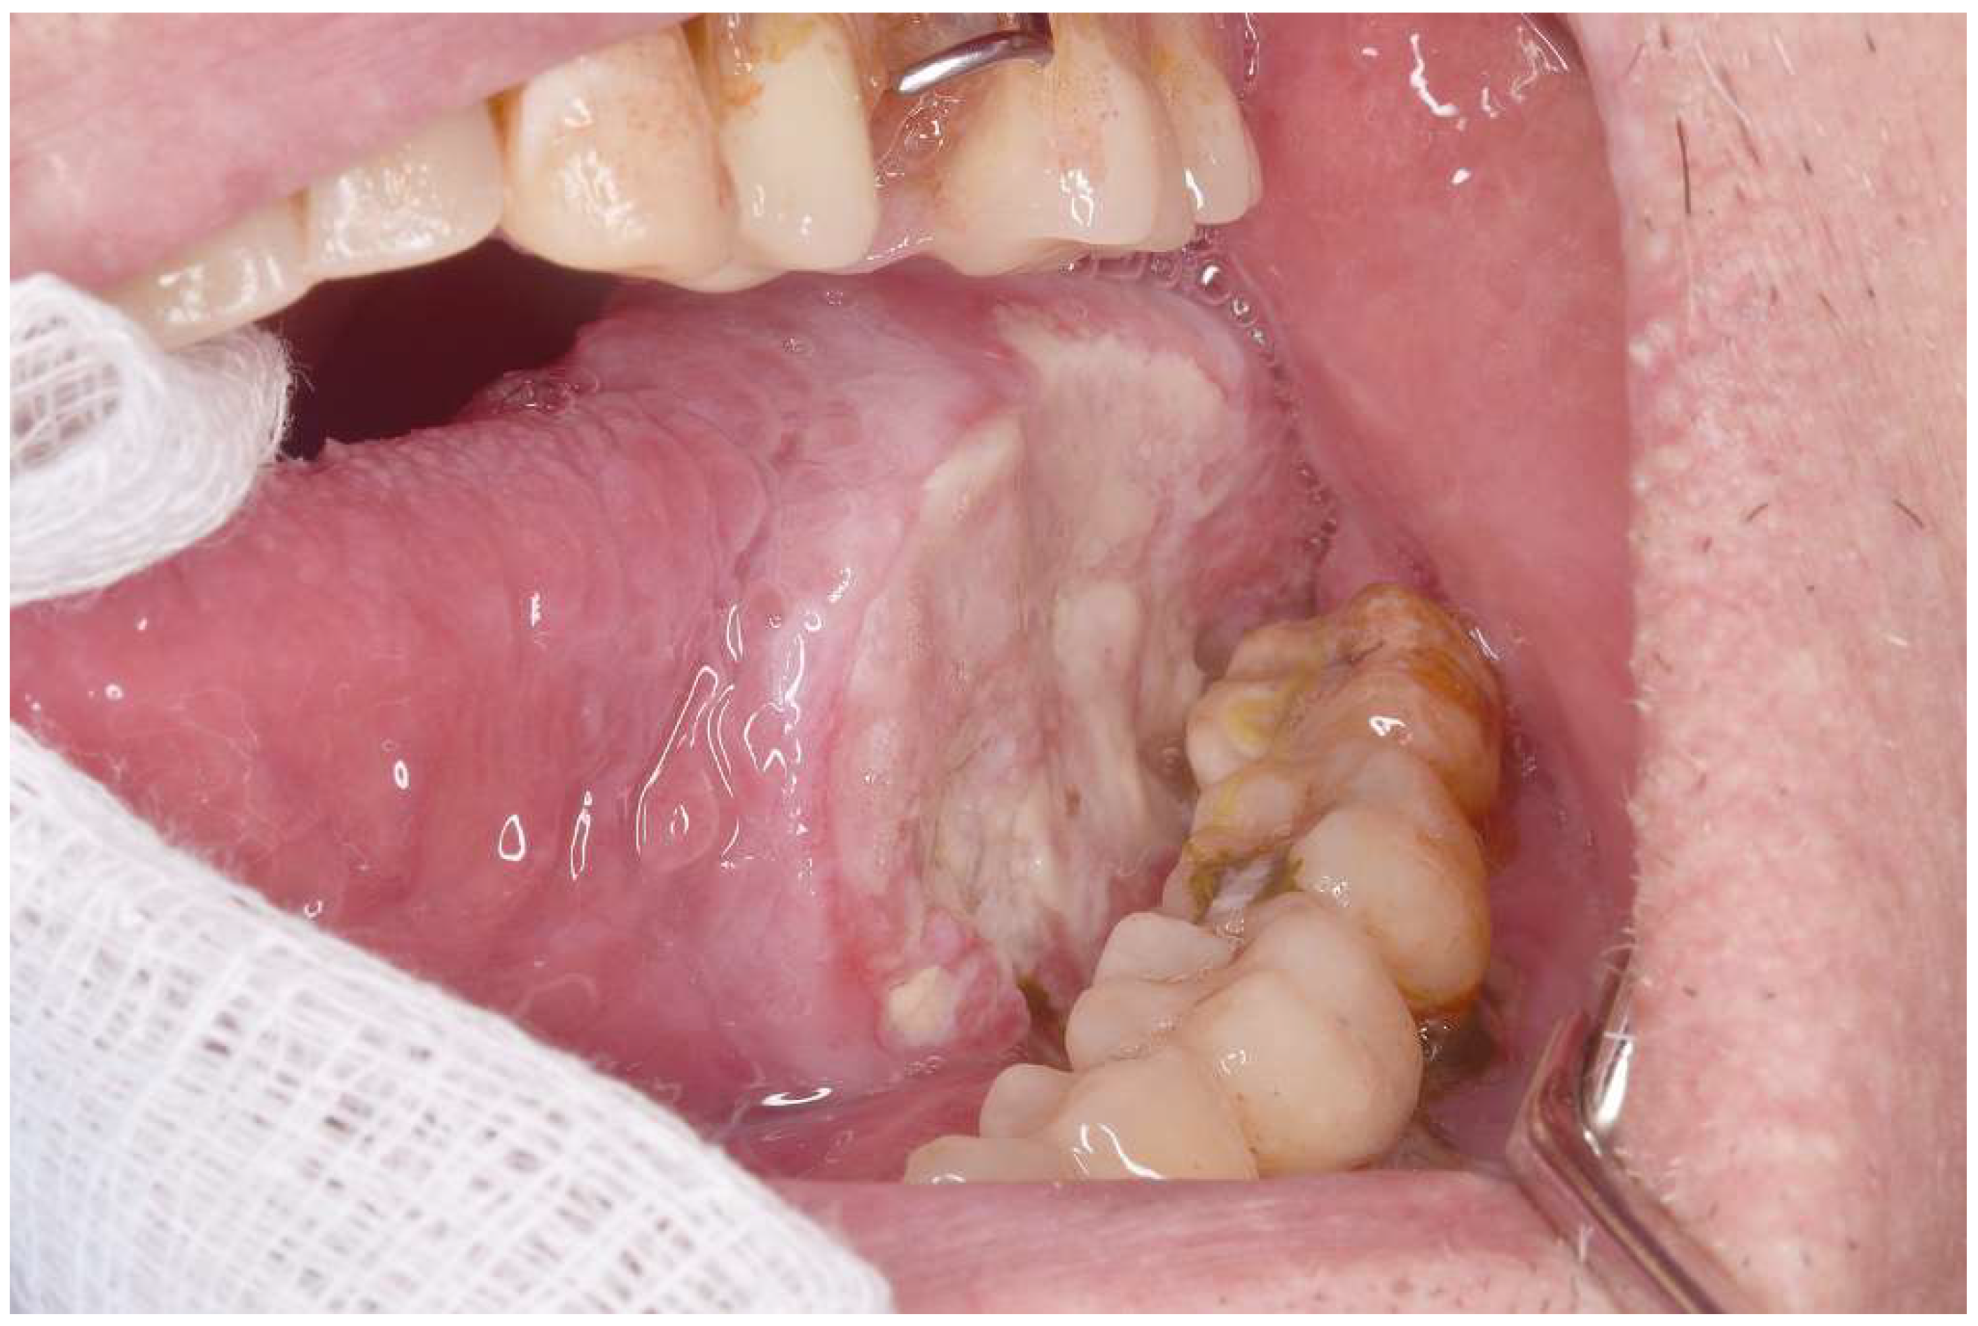

Background/Objectives: Proliferative verrucous leukoplakia (PVL) is the oral disorder with the greatest degree of malignant transformation. However, it is relatively rare. This study compared the clinical characteristics of patients with oral squamous cell carcinoma (OSCC) who had and had not been previously diagnosed with PVL. Methods: This case–control study compared the clinical characteristics of patients classified as early (T1 and T2) or advanced (T3 and T4) OSCC according to the TNM classification, including age, gender, location, and clinical type of cancer. The analysis involved 140 patients. Group 1: 50 OSCC patients with PVL (OSCC-PVL) and Group 2: 90 OSCC patients without PVL (OSCC-noPVL). Results: The patients with OSCC-PVL were younger than those with OSCC-noPVL, but this did not reach statistical significance. Regarding patient gender, those with OSCC-PVL were much more frequently female (70%), while OSCC-noPVL was more prevalent in men (65.5%) (p < 0.01). There were also significant differences in the oral locations between the two groups: the gingiva was most prevalent in OSCC-PVL and the tongue in OSCC-noPVL. Erythroleukoplastic forms were significantly more common in OSCC-PVL (30% vs. 7.7%), while ulcerated forms were more frequent in OSCC-noPVL (63.3% vs. 42%). Finally, early T stages were much more prevalent in our patients with OSCC-PVL. Conclusions: We found that OSCC preceded by PVL was much more frequent in women, had less aggressive clinical forms, and had significantly more frequent early T stages than in OSCC-noPVL.